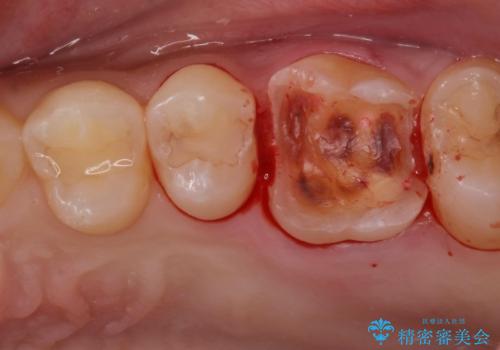

金の詰め物の中にある虫歯を除去してセラミック治療

- 金の詰め物の中が黒く透けていて虫歯があるので拡大鏡下で外し、虫歯がない事を確認した後、被せ物で治療しました。

一番奥の歯は古い樹脂の治療の後がありましたのでセラミックの詰め物で治療しました。